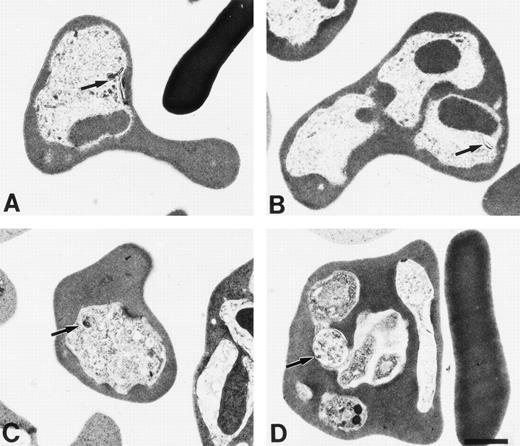

Erythrocytes were fixed for electron microscopy at the same time points as the blood smears were taken. The results (Fig 6) indicated that little hemozoin was present in HbF (Fig 6A), trophozoite, and (Fig 6B) schizont. Further, the hemozoin was not in food vacuoles. In contrast, in normal erythrocytes, there was more hemozoin and it was present in discreet vacuoles (Fig 6C) trophozoite (Fig 6D) schizont.

Electron micrographs of γ (A and B) and normal (C and D) mice infected with P chabaudi adami taken at 10:30am (A and C) and 6:30 pm (B and D).

Our results suggest that malaria parasites may not develop normally in erythrocytes containing HbF because the parasites cannot digest this hemoglobin as well as HbA. This leads to a delay in development of the parasite. Morphologically, this was apparent in the difference in blood stages at early and later time points, between normal and transgenic mice. Moreover, electron microscopy demonstrated that hemozoin is not synthesized normally in the γ mice. Similar results were reported forP falciparum grown in β-thalassemic RBC in medium deficient in essential amino acids, particularly in those containing HbF.21 22 Finally, the rate of digestion of HbF by a recombinant malarial human hemoglobinase is approximately half that of HbA. Taken together, these results provide a mechanism for the ability of HbF to protect the host from the lethality of malaria.